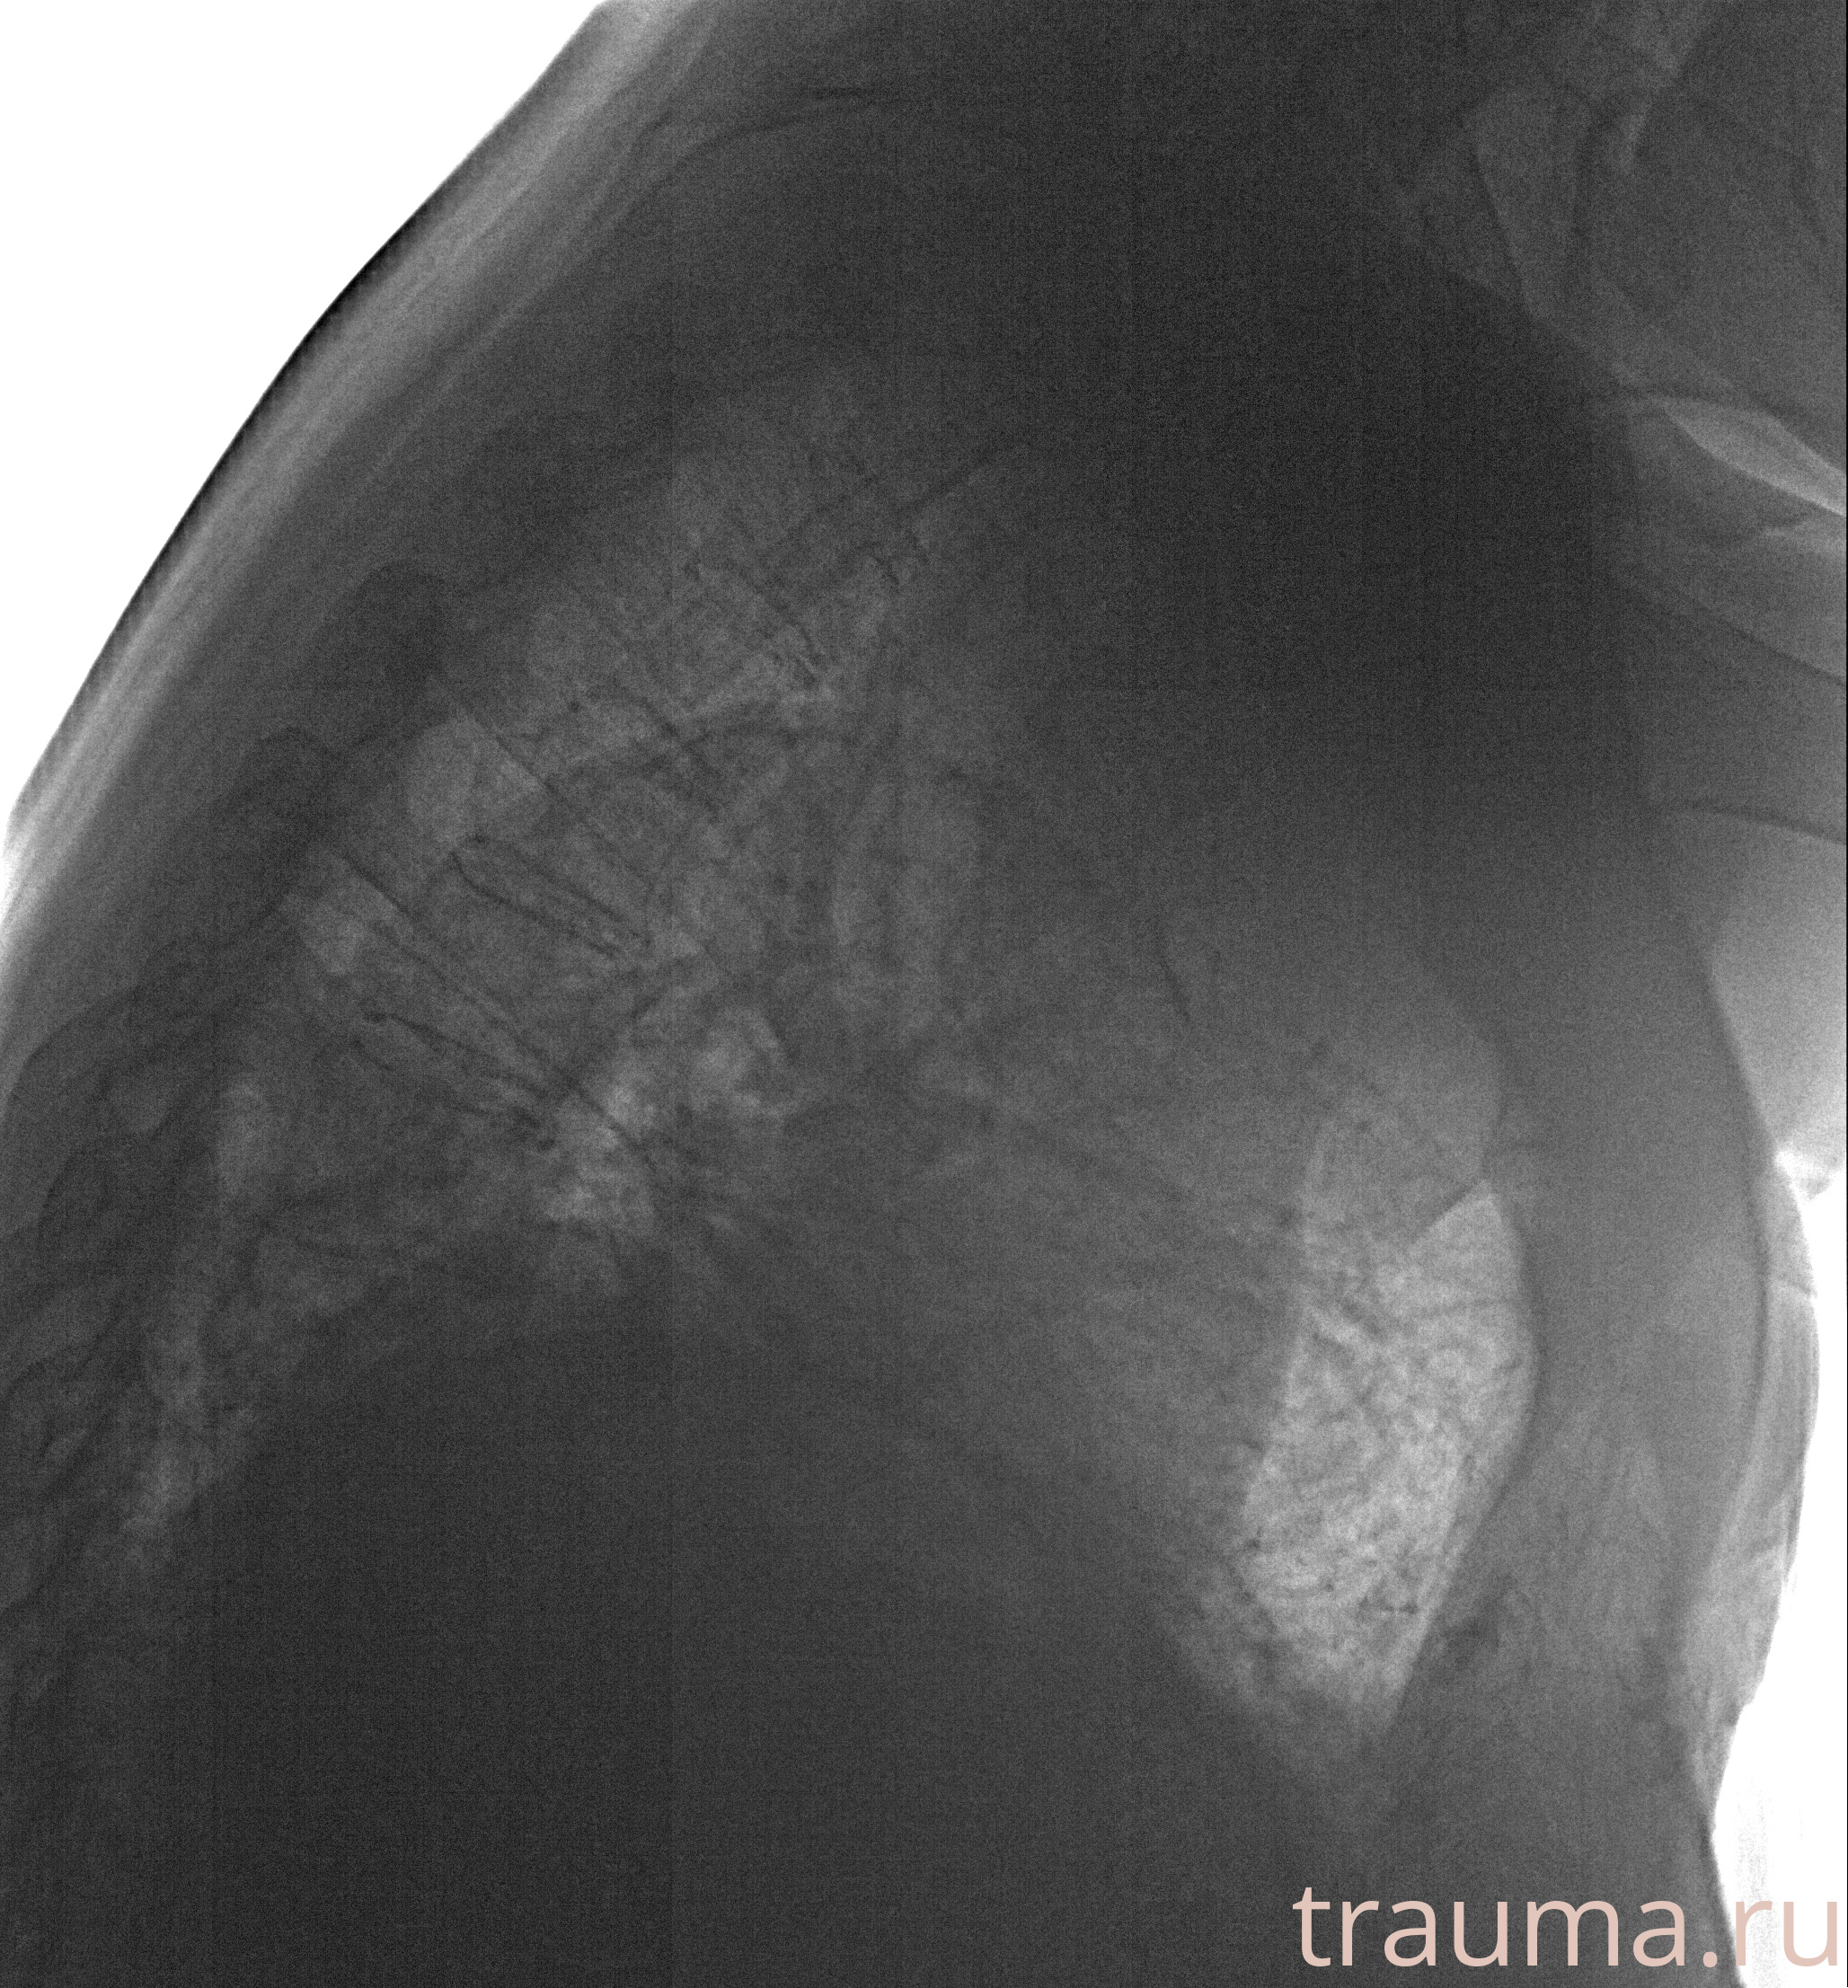

Рентген на дому: по вашему адресу приезжает врач-рентгенолог, травматолог-ортопед с мобильным рентгеновским аппаратом, проводит диагностику травмы или заболевания, делает необходимые рентгенограммы, дает рекомендации по дальнейшему лечению. Получить качественные снимки в домашних условиях возможно благодаря уникальной методике, разработанной МосРентген Центром для института  Склифосовского

при переломе шейки бедра и пневмонии от компании МосРентген Центр - партнера Института имени Склифосовского